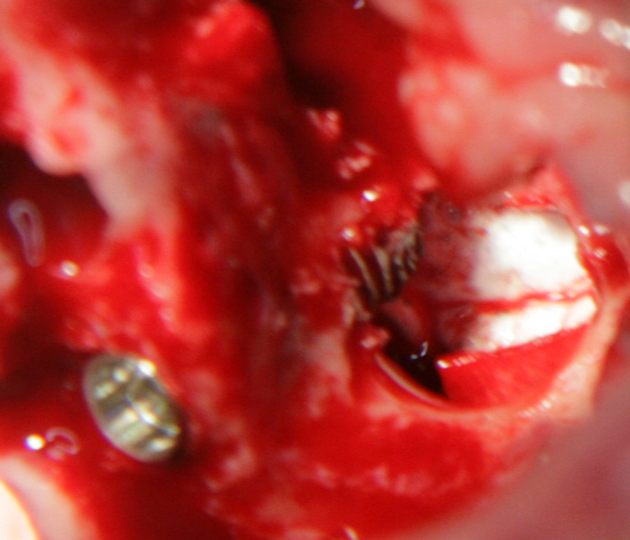

Видеоклип за открит синуслифтинг Пластинка Сasios